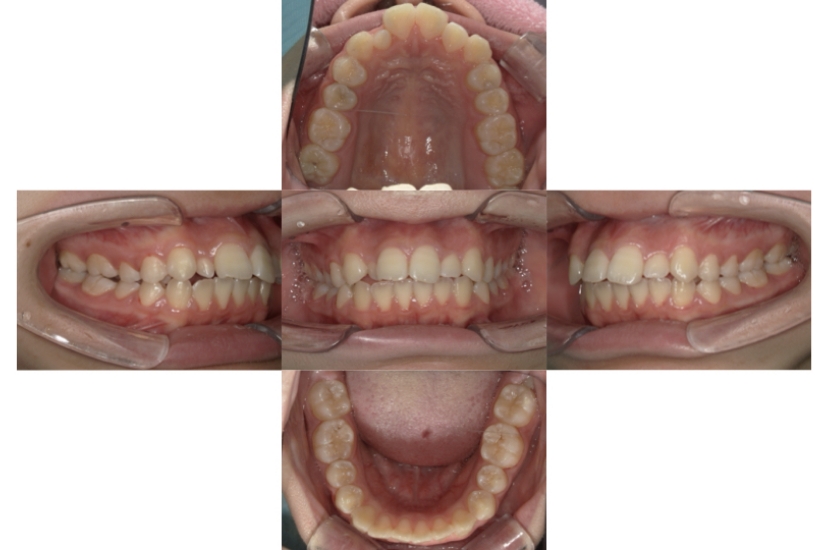

BEFORE

AFTER

上下顎叢生、反対咬合(上下の前歯のガタガタ、若干受け口)のケースです。

装置はラビアル(上下表側)で、上下顎の小臼歯を4本抜歯を行っています。抜歯したスペースを使って、上下の叢生改善と前歯の受け口の改善を行っています。

主訴 前歯のガタガタを治したい。

年齢・性別 45歳 女性

お住まいの地域 神奈川県川崎市

治療方針 抜歯スペースを利用して上前歯の叢生(ガタガタ)の改善と受け口の改善

抜歯部位 上顎左右第一小臼歯、下顎左右第二小臼歯

使用装置 ラビアル(上下表側)、顎間ゴム

治療期間 2年6か月

治療回数 20回

リテーナー クリアリテーナー